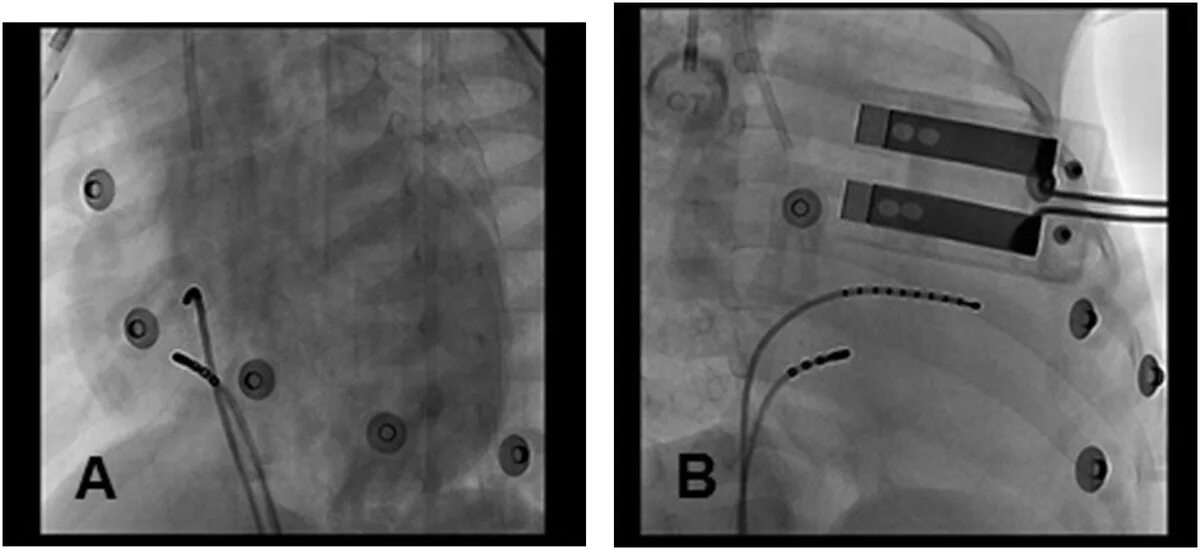

Рча сердца после операции